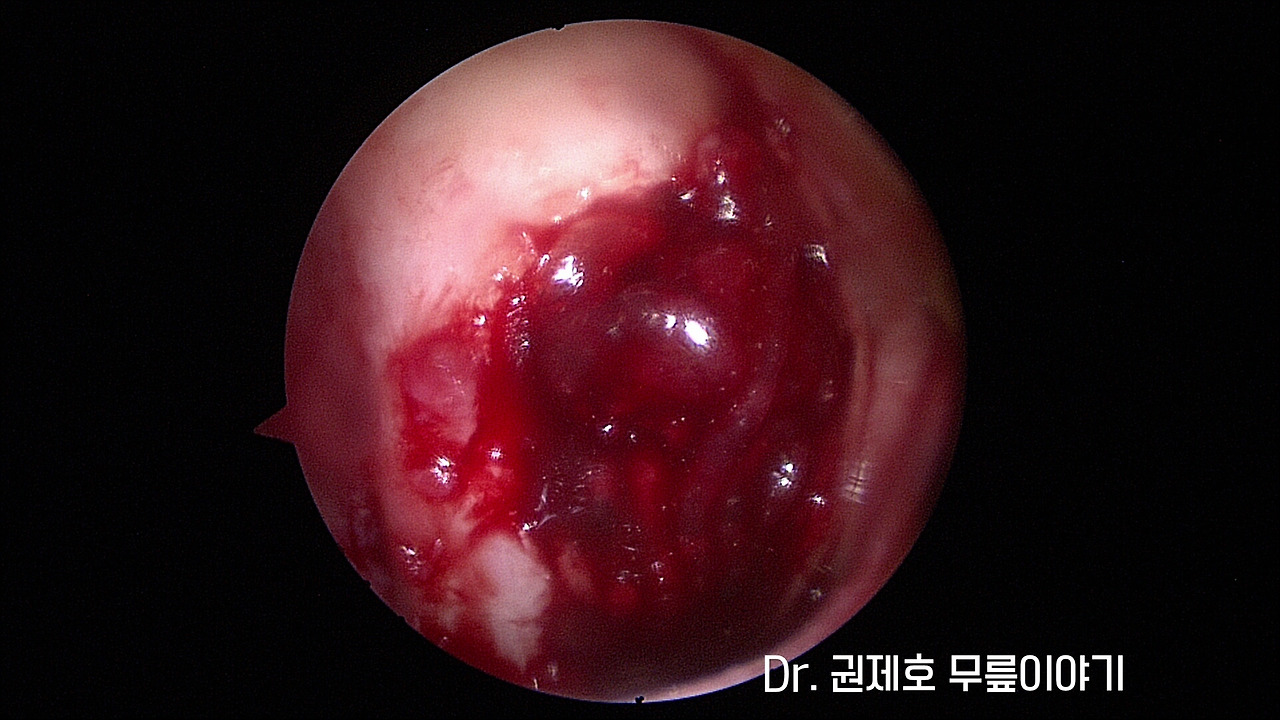

무릎연골줄기세포치료 (11).jpg

관절경을 이용하여 치료를 진행하게 되고, 사진에서 보면 무릎 연골이 결손 된 부위를 확인할 수 있습니다.